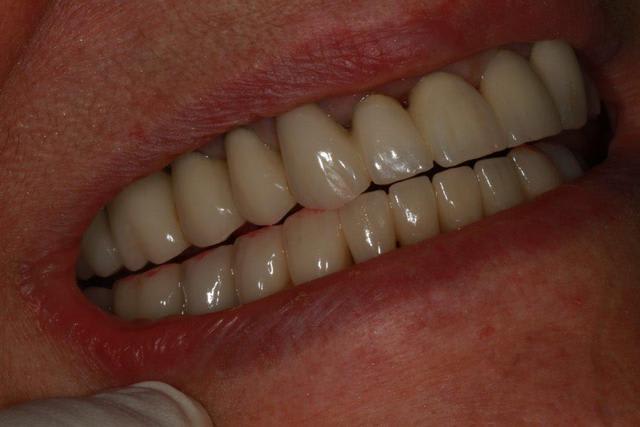

Enlaye, j'ai fait un contrôle avec papier rouge (épais)

ton avis?

Photo 1 dents serrées occlusion sans glissement

Photo 2 le bas après papier rouge

Photo 3 le haut après papier rouge

Photo 4 le bas après retouche et papier rouge

Photo 5 le haut après retouche et papier rouge

Photo 6 latéralité gauche

Photo 7 latéralité droite

La sensation de "rigidité" pour le maxillaire sup s’estompe, la patiente s'approprie ses nouvelles prothèses.

le petit "truc" concernant l'implant semble fonctionner...à merveille.